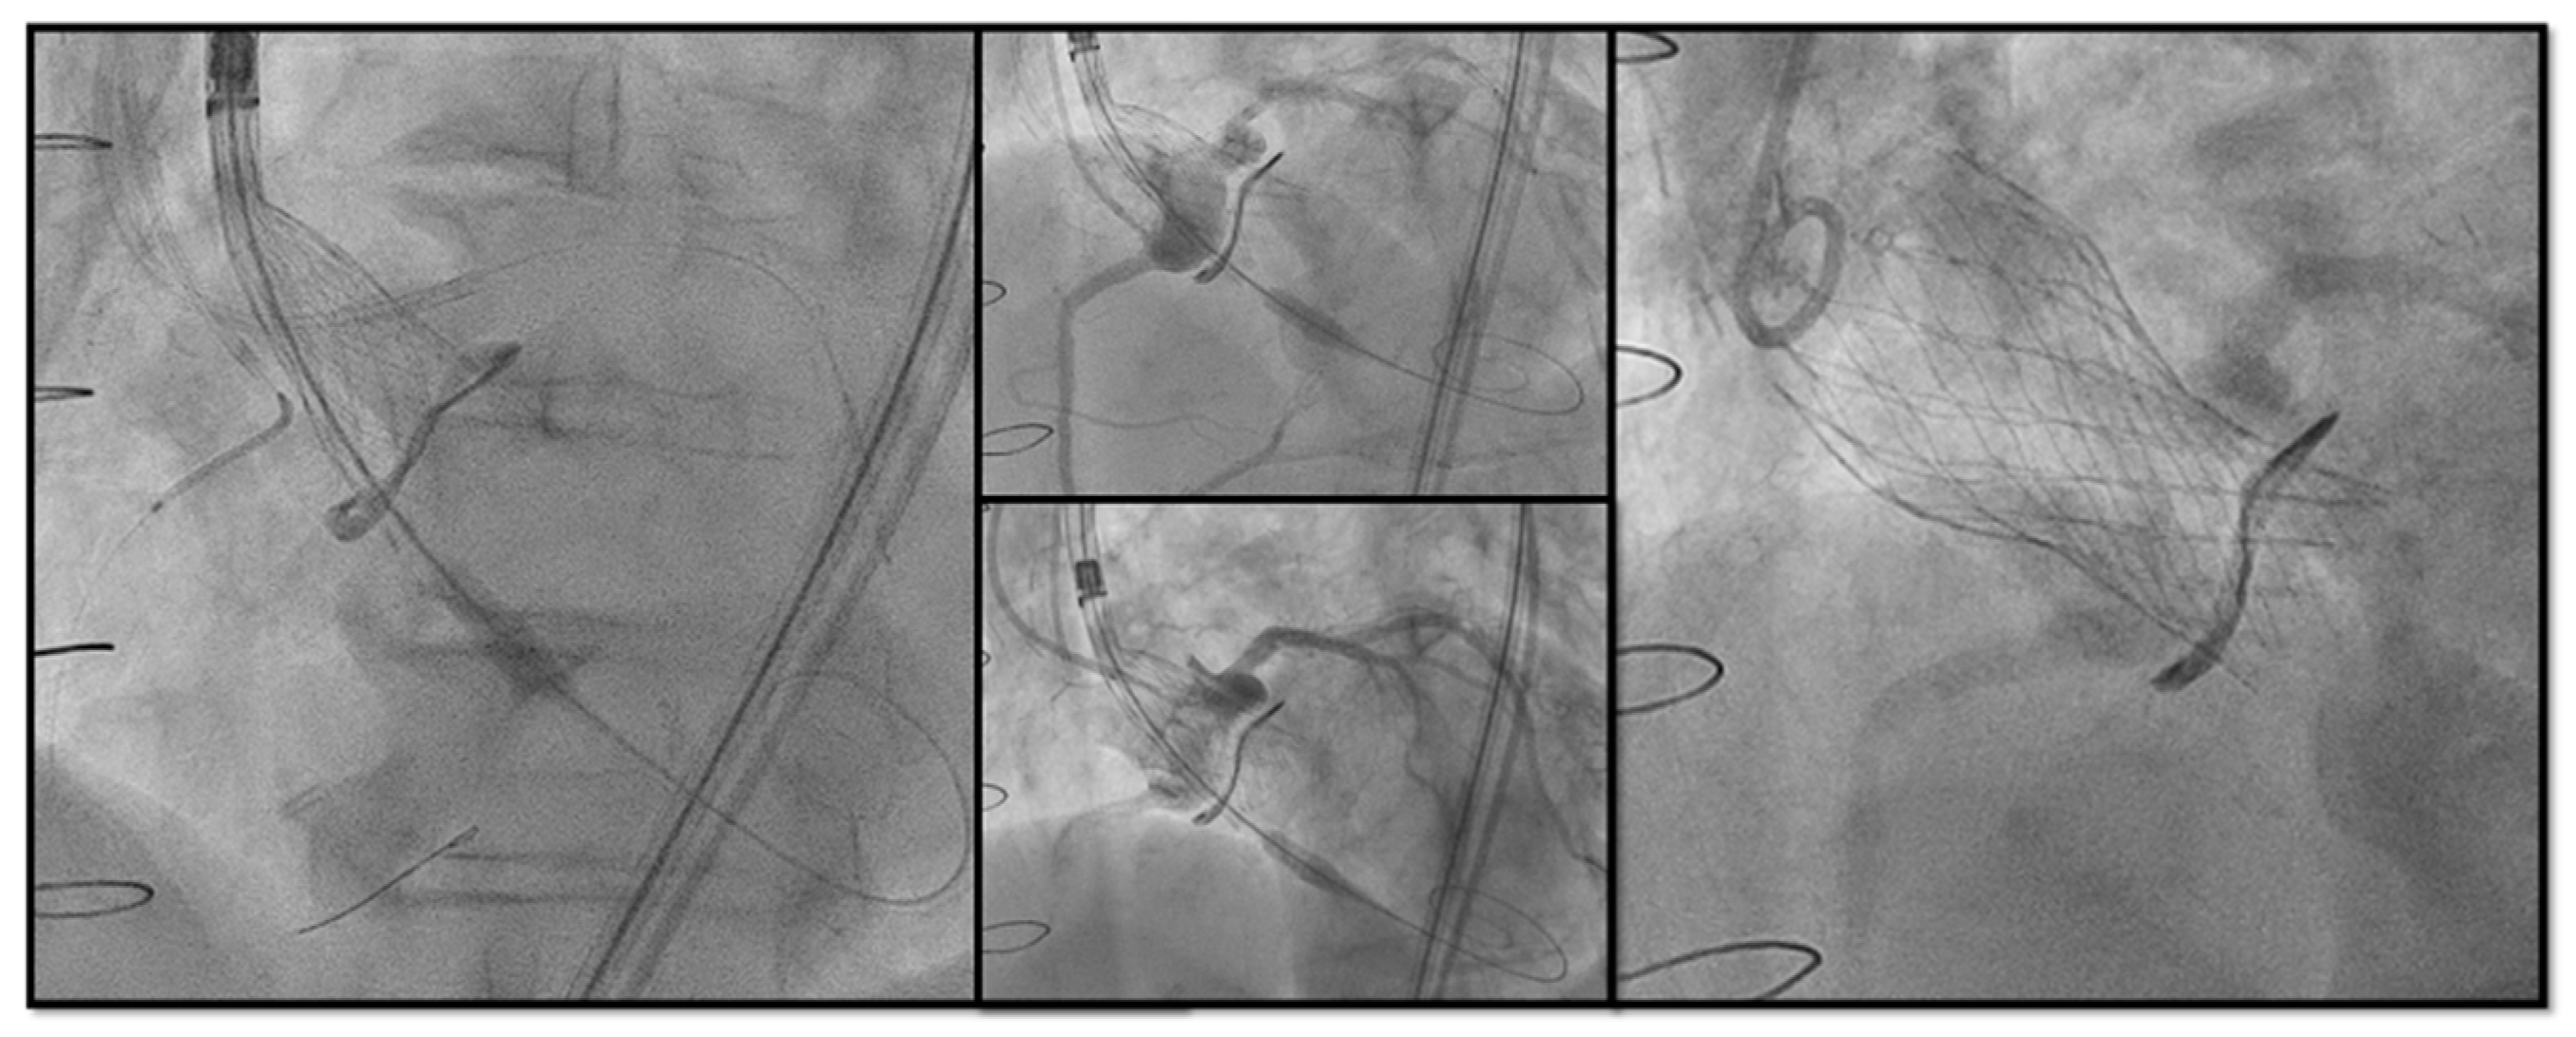

- The timing of BVF, either before or after TAVR, remains controversial. BVF after THV implantation leads to better hemodynamics but carries a risk of damaging new prosthesis; BVF before THV implantation ensures better sealing, but may cause embolization of SHV, acute valvular regurgitation and hemodynamic instability [40,41]. The general practice is to do BVF after THV if using BEV so the NC balloon simultaneously fully expand the THV and fracture the surgical prosthesis while SEVs may not have enough force to fully expand a degenerated SHV and will benefit from balloon fracture before and if needed, even after implantation (Figure 6).

Figure 6. (A) Bioprosthetic valve fracture with a True Balloon 20 balloon after valve-in-valve with Corevalve Evolut Pro + n.23 implantation in a Mitroflow 19 (LCA protection without final stent implantation) (B) IVUS shows patency of the VS with a minimum distance between aortic wall and prosthetic leaflet of 2.2 mm at STJ. LCA: left coronary artery; IVUS: intra-vascular ultrasound; STJ: sino-tubular junction distance.